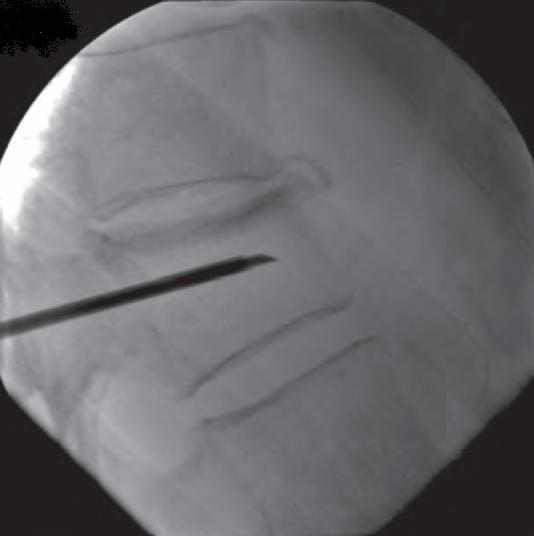

Imagem de raio-x intra-operatório com agulha locada próximo ao centro do corpo vertebral.